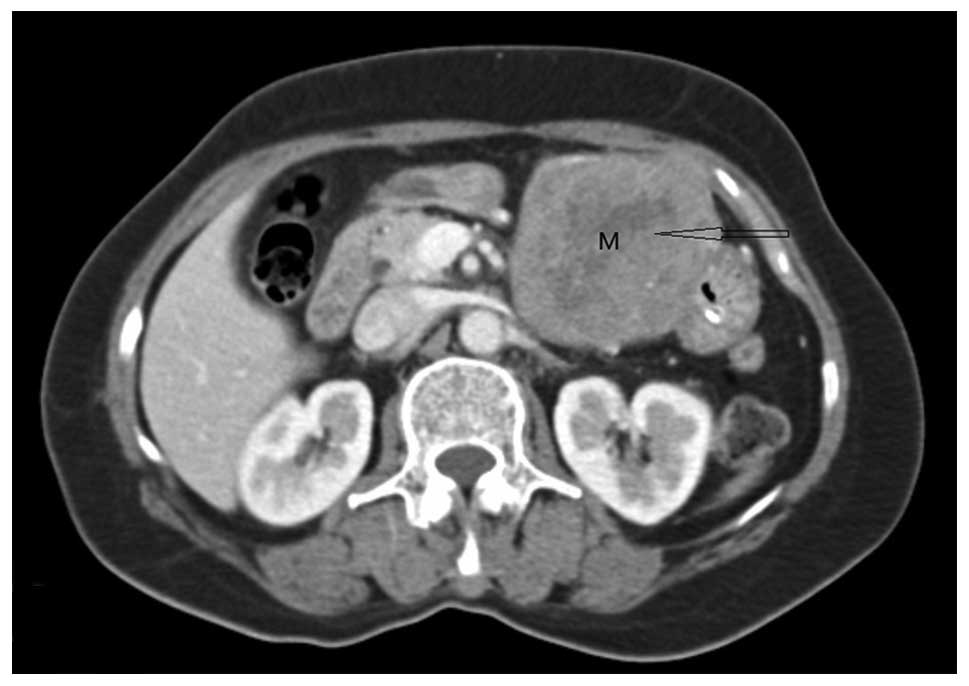

This abdominal ct scan shows tumor masses malignant lymphomas in the area behind the peritoneal cavity retroperitoneal space.